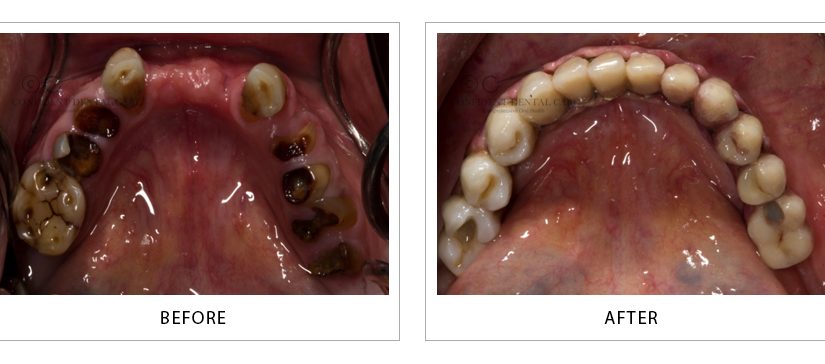

Full Mouth Implant